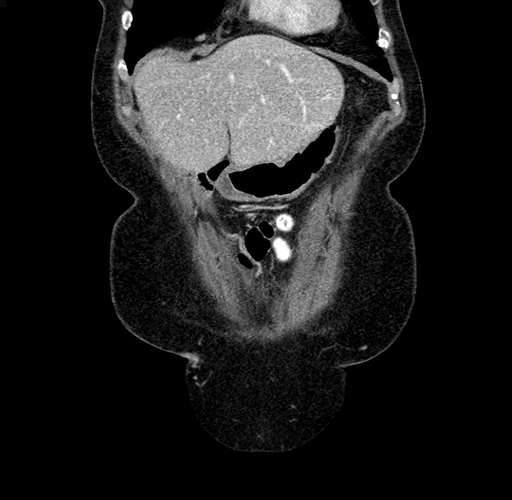

Pre-Chemo: Coronal Venous